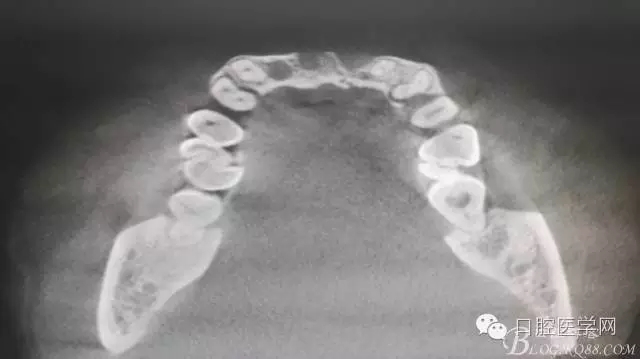

為他院轉診患者。男,無吸煙史,前牙因齲壞治療后,外力折斷導致拔除?,F拔除該牙后兩個多月。 左上區(qū)域骨寬度不足,計劃植入種植體同期GBR。

左上區(qū)域骨寬度不足,計劃植入種植體同期GBR。